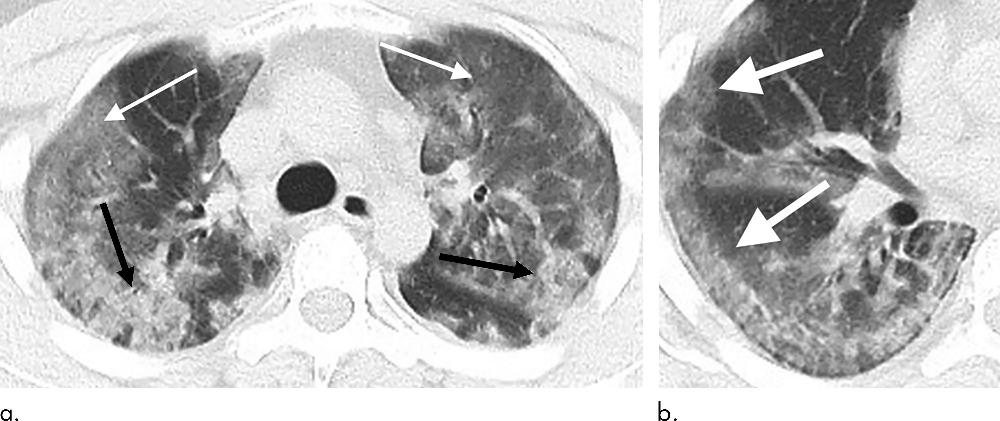

Figure 1. 29-year old male with unknown exposure history, presenting with fever and cough, ultimately requiring intensive care unit admission. (a) Axial thin-section non-contrast CT scan shows diffuse bilateral confluent and patchy ground-glass (solid arrows) and consolidative (dashed arrows) pulmonary opacities. (b) The disease in the right middle and lower lobes has a striking peripheral distribution (arrow).